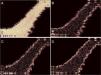

A wavelet transform is applied in the segmented image (Fig. 3C). In this study, the biorthogonal transform (bio3.5) was chosen to decompose images in horizontal, vertical, and diagonal directions. When applying the wavelet transform, the approximation of the original image is also computed. The wavelet transform may be applied to many levels using the computed approximation. Fig. 4 shows an example of one level wavelet transform applied in Fig. 3C, resulting in an approximation (Fig. 4A), and decomposed images in horizontal (Fig. 4B), vertical (Fig. 4C), and diagonal (Fig. 4D) directions.

Results of wavelet transform application for one level. In this example, wavelet transform was applied in Fig. 3C resulting in an (A) approximation, and decomposed images in (B) horizontal, (C) vertical, and (D) diagonal directions.